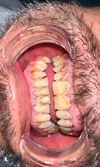

تسوس الأسنان

أمراض الأسنان واللثة